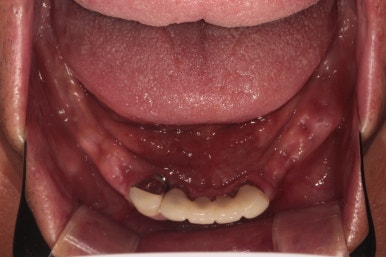

원가이드를 활용하여 2주 후 아래턱 임플란트 수술!

약 2주 후 아래턱 임플란트 수술을 시행하였습니다.

개수가 조금 더 적어보이는 것은, 아래턱 뼈가 위턱뼈보다 더 딱딱하기 때문입니다.

비교적 적은 임플란트로도 성인 남성의 씹는 힘을 견딜 수 있거든요!!!

이렇게 오른쪽 아래부터 임플란트 2차 수술을 시행했습니다.

왼쪽 아래는 뼈이식을 많이했어서, 조금 더 기다리고 있는 모습입니다.